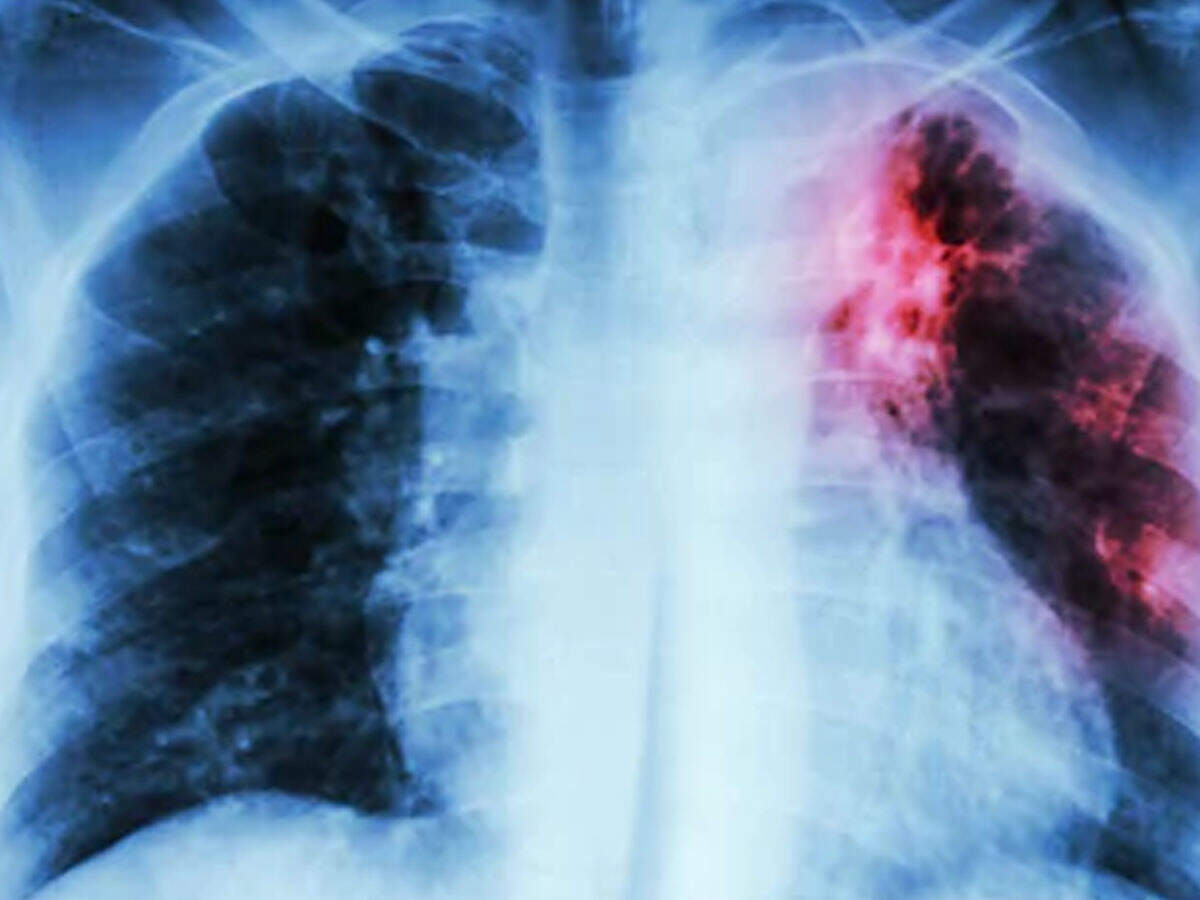

“There is a high possibility of consumers getting infected with communicable diseases because of any infected food handler. Hence we conducted this drive and screened around 2,972 workers out of which 98 were suspected to have tuberculosis. Further, post the results if we come across any positive patients, then we will immediately start their treatment. If a worker is infected and he sneezes or coughs near the food, then there are chances of the germs spreading, which will affect the consumers,” said Dr Ram Kendre, civic medical health officer.